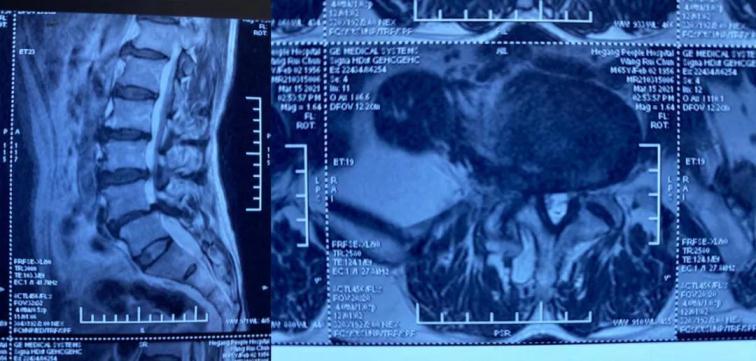

患者王某,男,65歲,腰痛伴右下肢麻痛1年,坐起及行走時疼痛明顯加重,行走不足100米即疼痛難忍需要休息,保守治療無效,嚴(yán)重影響生活質(zhì)量。慕名來到我院并找到喬院長尋求治療。患者入院后,經(jīng)過喬院長認(rèn)真細(xì)致的檢查,診斷為:腰椎管狹窄、腰椎滑脫。

術(shù)前MRI